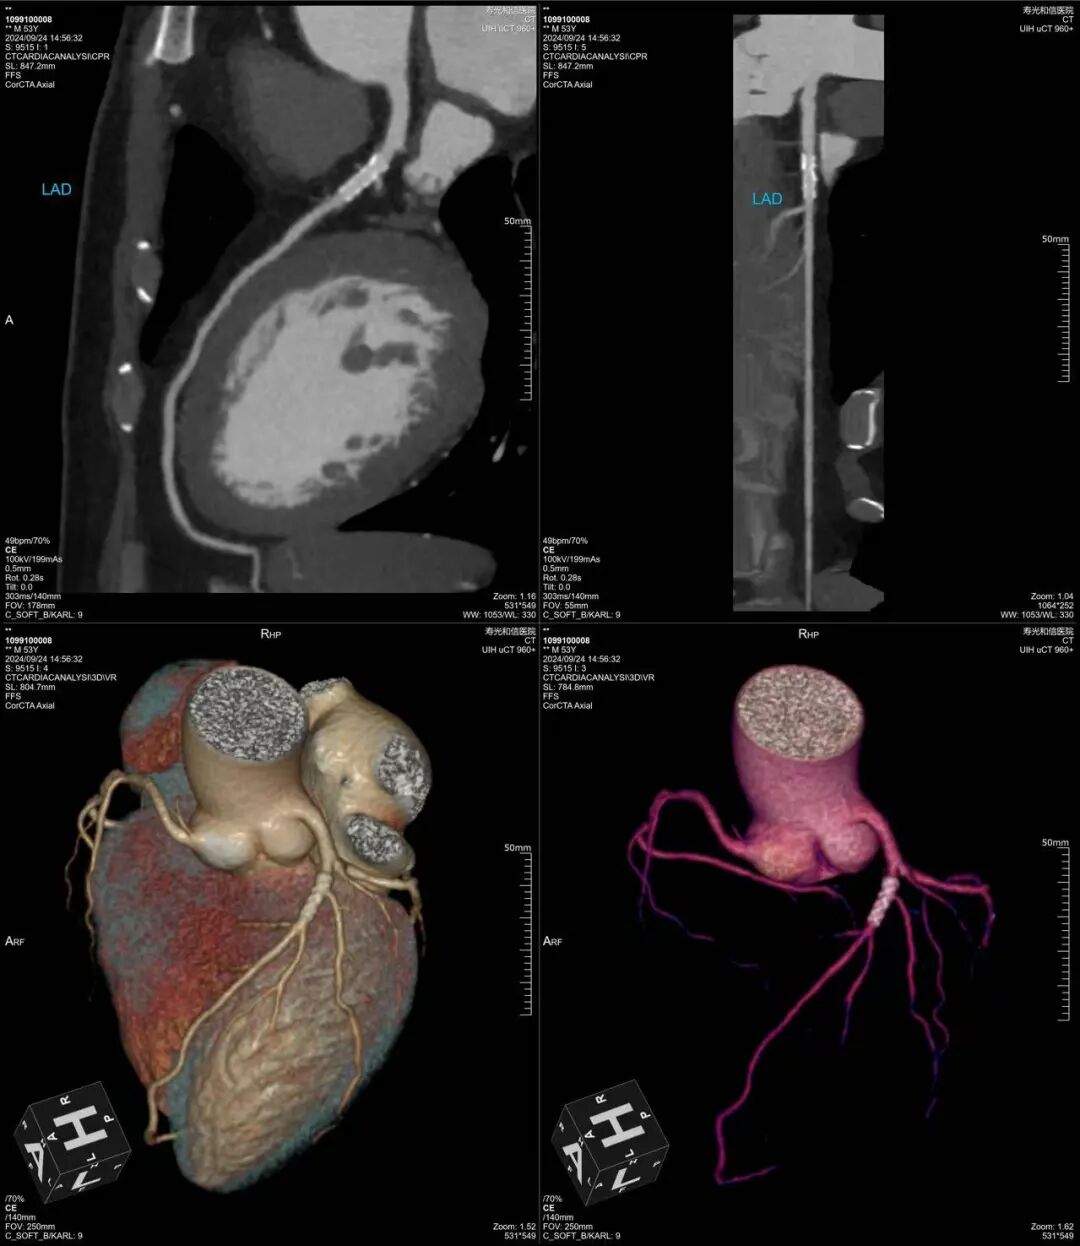

心脏搭桥术后

冠状动脉多发混合斑块形成并重度狭窄

640层意味着扫描极薄、极细腻,冠脉上有没有斑块、斑块是什么性质、狭窄程度多少,看得一清二楚。钙化、软斑块、混合斑块,都逃不过它的“眼睛”。

如果CTA发现明显狭窄、需要进一步处理,我们还有DSA(数字减影血管造影)——这是诊断冠脉狭窄的“金标准”,检查的同时就可以直接介入治疗,一步到位。